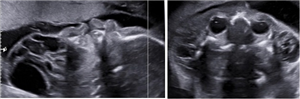

CLS: Xuất huyết nội sọ trong thai kỳ